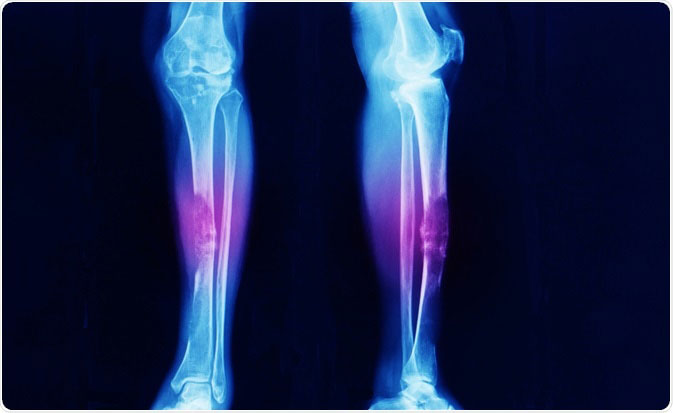

เป็นมะเร็งที่ต่อมน้ําเหลืองระยะ 4 ได้รับการรักษาด้วยเคมีบําบัด 8 คอร์ส ต่อมาลุกลามไปที่กระดูกขาขวา ทําให้กระดูก ขาหัก มีรอยดําที่กระดูกกะโหลกศีรษะ มีก้อนที่ไตด้วย แต่ไม่ได้ตัดชิ้นเนื้อตรวจจึงยังไม่ทราบแน่ชัดว่าใช่เป็นก้อนมะเร็งหรือไม่ แต่ก้อนนี้หายไปหลังให้เคมีบําบัด ต่อมารักษาอาการที่ขาขวาโดยครั้งที่หนึ่งด้วยการผ่าตัดใส่เหล็กที่ขาขวา และฉายแสงตรง บริเวณที่ผ่าตัดขาเพื่อกระตุ้นให้กระดูกงอก แต่กลับไม่งอก ยังคงมีช่องว่างของกระดูกอยู่ ต่อมาครั้งที่สองจึงผ่าตัดกระดูก ขาขวาอีกครั้งเพื่อปลูกถ่ายกระดูก แต่กลับไม่ประสบความสําเร็จ นั่นก็คือกระดูกที่มาปลูกใหม่ยังไม่ติดกัน จึงมีอาการปวด ขาขวา ยิ่งลงน้ําหนักตอนเดินยิ่งปวด ร่างกายซูบผอม อ่อนเพลีย เดินโดยอาศัยไม้ค้ำยัน และมีความวิตกกังวลอยู่ 2 เรื่องคือ

เมื่อวันที่ 1 พฤษภาคม 54 พอได้ 2 สัปดาห์ สังเกตเห็นว่าผิวพรรณมีการเปลี่ยนแปลง รู้สึกสดชื่น กระชุ่มกระชวย ไม่เพลีย นอนหลับดี เมื่อครบ 3 เดือนเอกซเรย์กระดูกขาตรงที่มีช่องว่าง เริ่มมีเงาให้เห็นรางๆ แสดงว่าเริ่มมีกระดูกงอก พอครบ 6 เดือน เอกซเรย์กระดูกขา กระดูกงอกเพิ่มกว่าเดิมอย่างเห็นได้ชัด ครบ 1 ปี (15 พ.ค.55) ผลการเอกซเรย์กระดูกขาชี้ว่า กระดูกติดดีแล้ว ไม่มีช่องว่าง ซึ่งก็หมายความว่าเซลล์มะเร็งที่กระดูกถูกยับยั้งไปแล้ว กระดูกจึงสามารถสร้างเชื่อมติดกันได้ จนแพทย์ขยายเวลานัดเพื่อติดตามเรื่องกระดูกเป็นปีละ 1 ครั้ง และน้ําหนักเพิ่มขึ้น 3 ก.ก. (จาก 51 เป็น 54 ก.ก.) อาการปวดขาลดลง เดินได้เกือบ เหมือนเดิม ไม่ต้องใช้ไม้เท้าแล้ว แม้ว่าเดินกะเผลกอยู่บ้าง มีปวดขาบ้างคงเกิดจากโลหะที่อยู่ข้างในอาจเสียดสี หรือทับเนื้ออยู่บ้าง แต่ก็พอใจแล้วค่ะ ตลอดเวลาที่ *